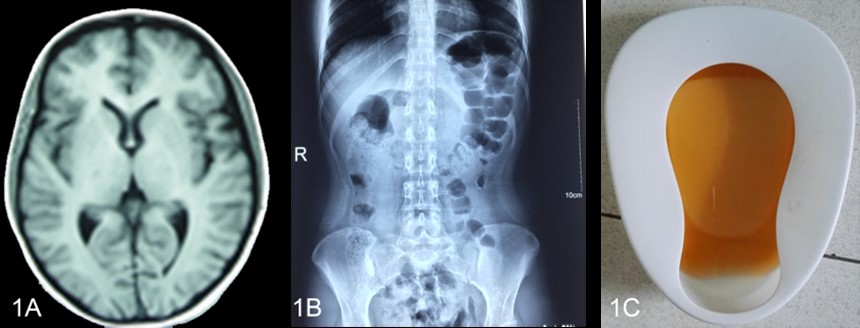

A 头颅MRI显示正常 B腹部平片示肠胀气 C 棕色尿液

图1-1 先证者发作的临床资料